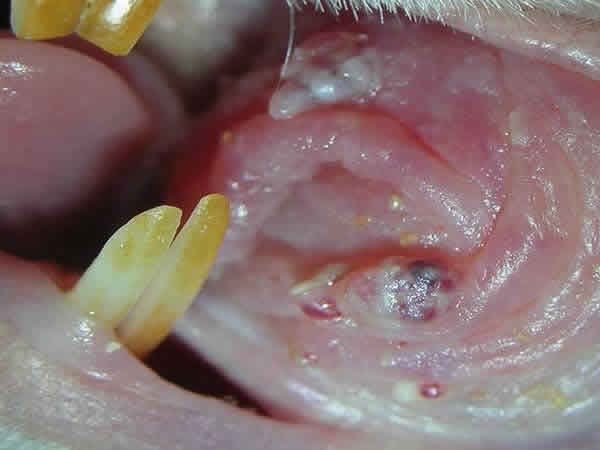

Fig. 3: lesiones multicéntricas en la mucosa yugal de un hámster (modelo II) tras 8 semanas de tratamiento con DMBA.